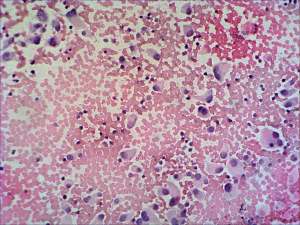

Cytological picture. There was no colloid in the background. There were enlarged atypical epithelial cells with eccentric nuclei without forming any structure resembling that of follicles. Many binucleated cells could be seen Some nuclei contained intranuclear inclusion. Preliminary cytological diagnosis: suspicion of malignancy.

Calcitonin immunocytochemistry: was positive and serum-calcitonin was elevated.

Final diagnosis: medullary cancer.